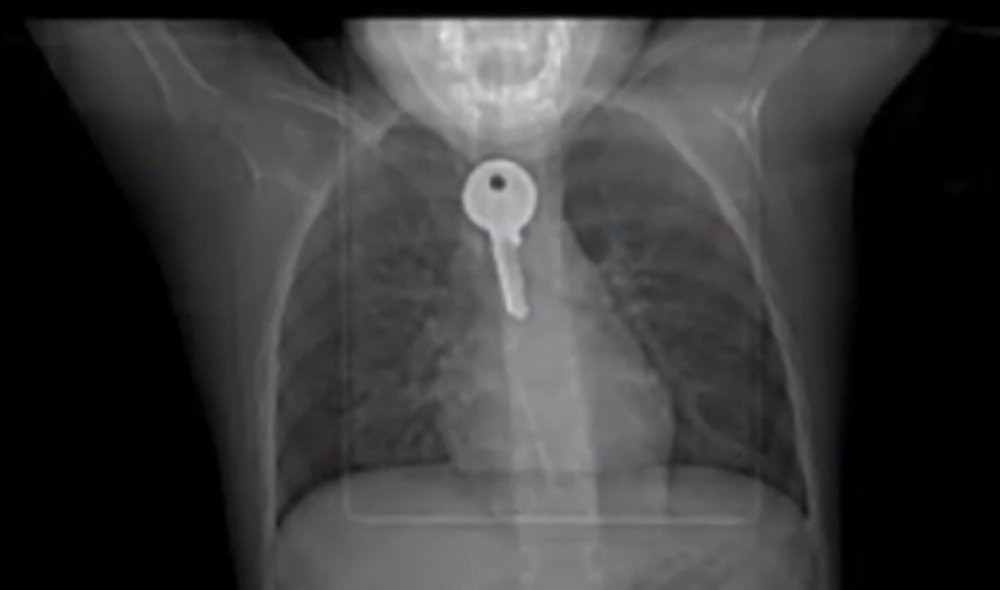

Hình ảnh phim chụp X - Quang dị vật là chiếc chìa khóa mắc kẹt trong thực quản bệnh nhi. (Ảnh: Bệnh viện cung cấp)

Tại đây, qua hình ảnh phim chụp x-quang, các bác sĩ thấy dị vật là chiếc chìa khóa đang mắc kẹt tại thực quản của bệnh nhi. Gặng hỏi thì bé cho biết, khi đang chơi gần tủ tại nhà, bé có nhặt được chiếc chìa khóa và vô tình nuốt phải, vì sợ nên bé không dám nói với bố mẹ.

Các bác sĩ đã nội soi cấp cứu gắp dị vật là chiếc chìa khóa đã gỉ sét dài 4 - 5cm. Hiện sức khỏe bệnh tương đối ổn định.